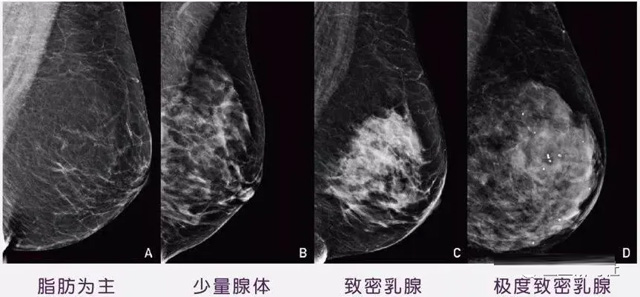

女性乳腺的自我检查,特别是注意有小结节,肿块,乳头有液体渗出情况,需要通过乳腺DR,X光线,磁共振等影像技术检查。胸的大小跟乳腺癌没多大关系,乳腺的密度大发病率高一些,胸小脂肪少致密性大。更容易乳腺癌。这个还不能通过自我检查来确认。致密乳腺组织看上去是白色或浅灰色需要通过乳腺X射线检查。

乳腺X射线有辐射,40岁以下的女性没有高危因素跟临床特征,医生都是不建议使用钼靶检查。乳腺超声无创无辐射,对乳腺组织分辨率高。可以将乳腺肿块从致密型乳腺组织中轻松查出来,多普勒模式检查乳腺及病变,超声小于1厘米的病灶非肿块性乳腺癌检出率低。超声检查结果依赖医生水平和经验,乳腺DR超声推动乳腺超声图像的标准化,提高检查的准确率。对乳腺组织内的细小钙化灶, 从范围、乳腺X射线形态以及分布特点上进行定性诊断。造影剂增强型乳腺X线摄影静脉注射碘化造影剂结合乳房X线摄影。磁共振MRI对乳腺癌研究的深入对软组织具有较高的分辨率等特点,在临床上被广泛认可。乳腺CT的探测器围绕着乳房成像,无痛无挤压,3D乳房图像乳腺病灶的大小、数量、形状、位置以及血管分布。一次扫描可创建多达两千张投影图像 。乳腺PET,适合普通人群和乳腺癌高危人群早期检测,发现极早期微小病灶并明确定性。